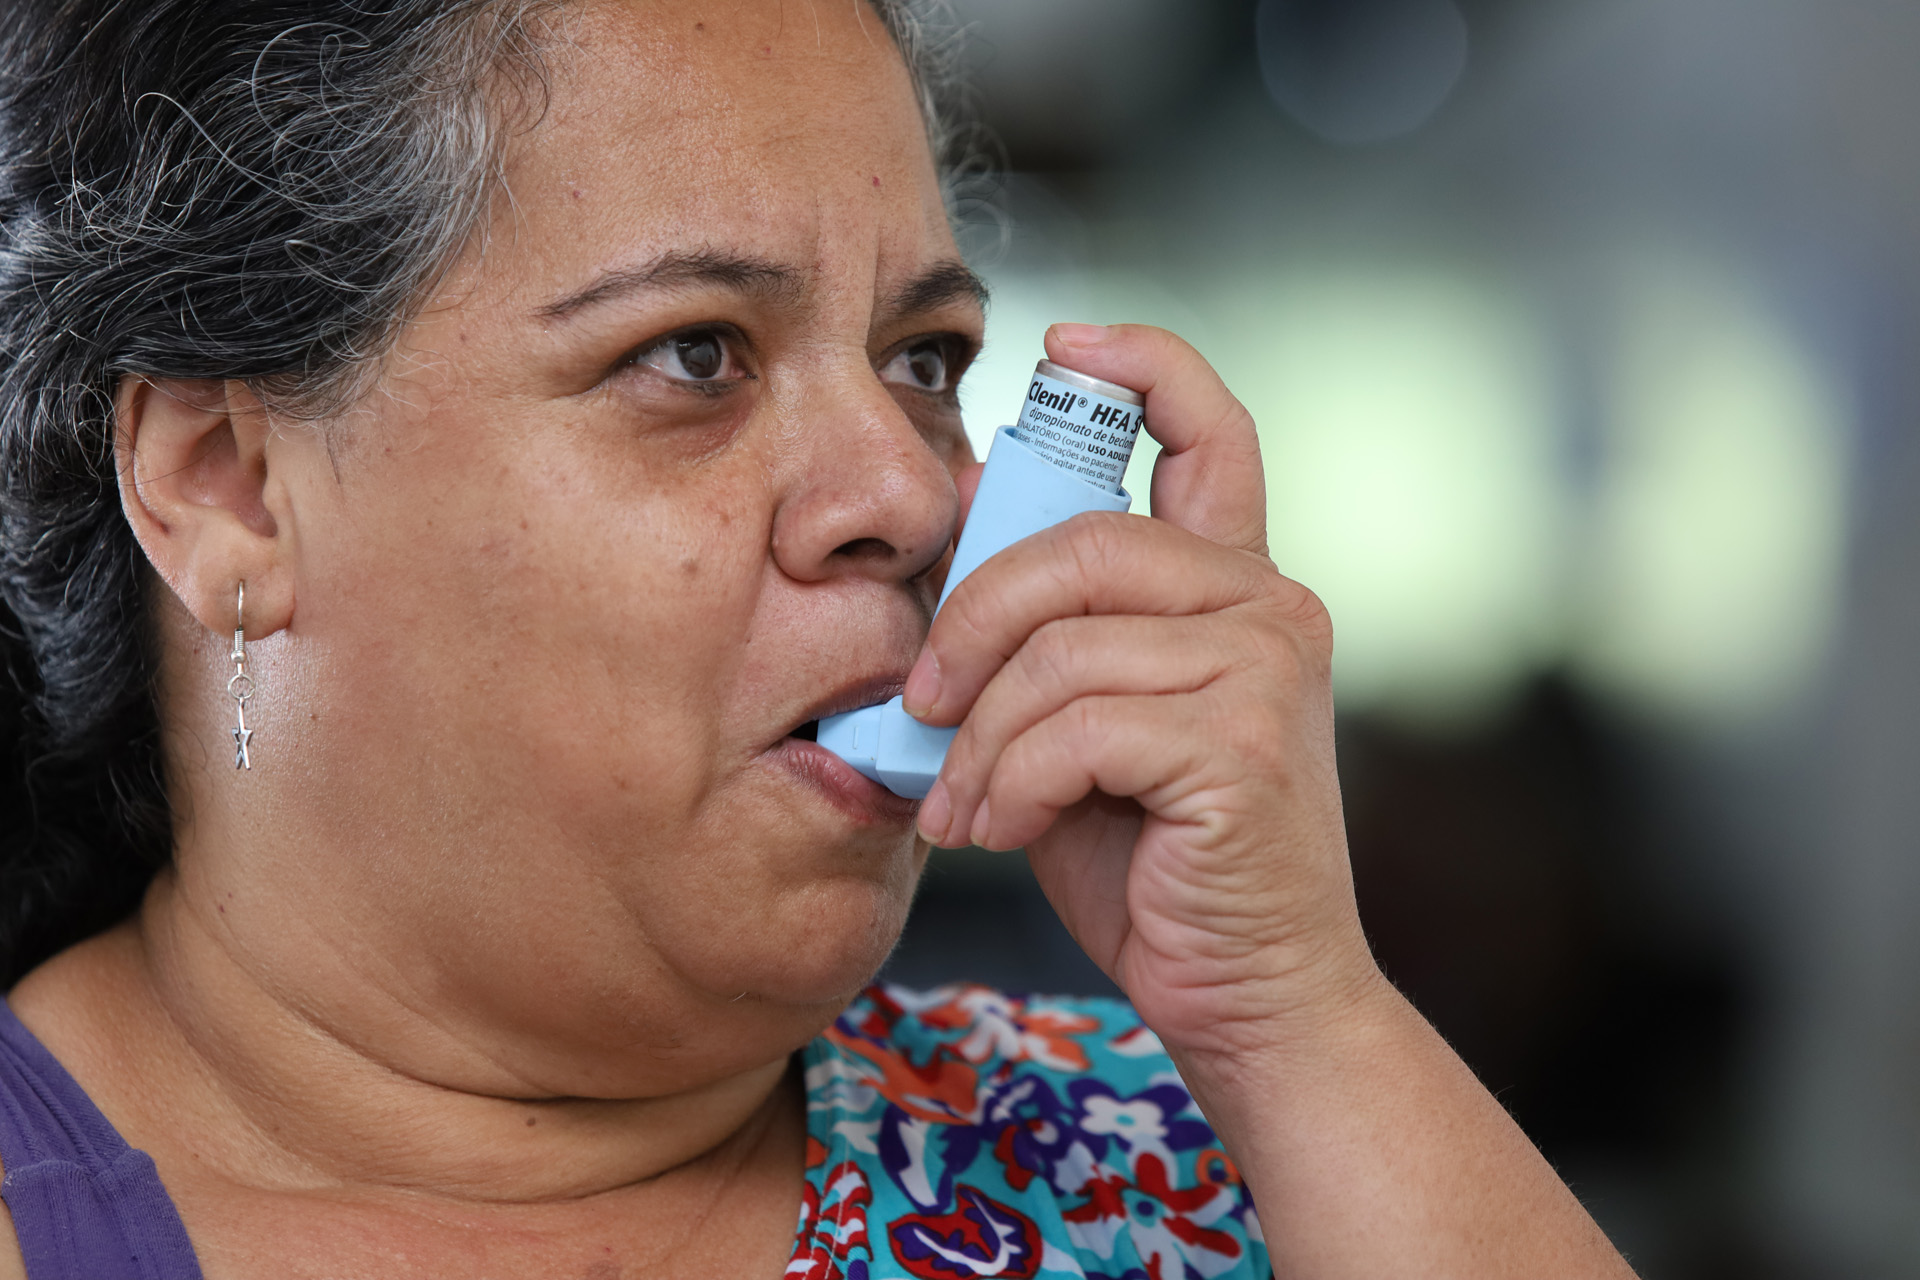

Temporada de gripe pode agravar crises de asma; veja como evitar

Falta de ar, chiado, sensação de pressão no peito, tosse e cansaço ao falar são…